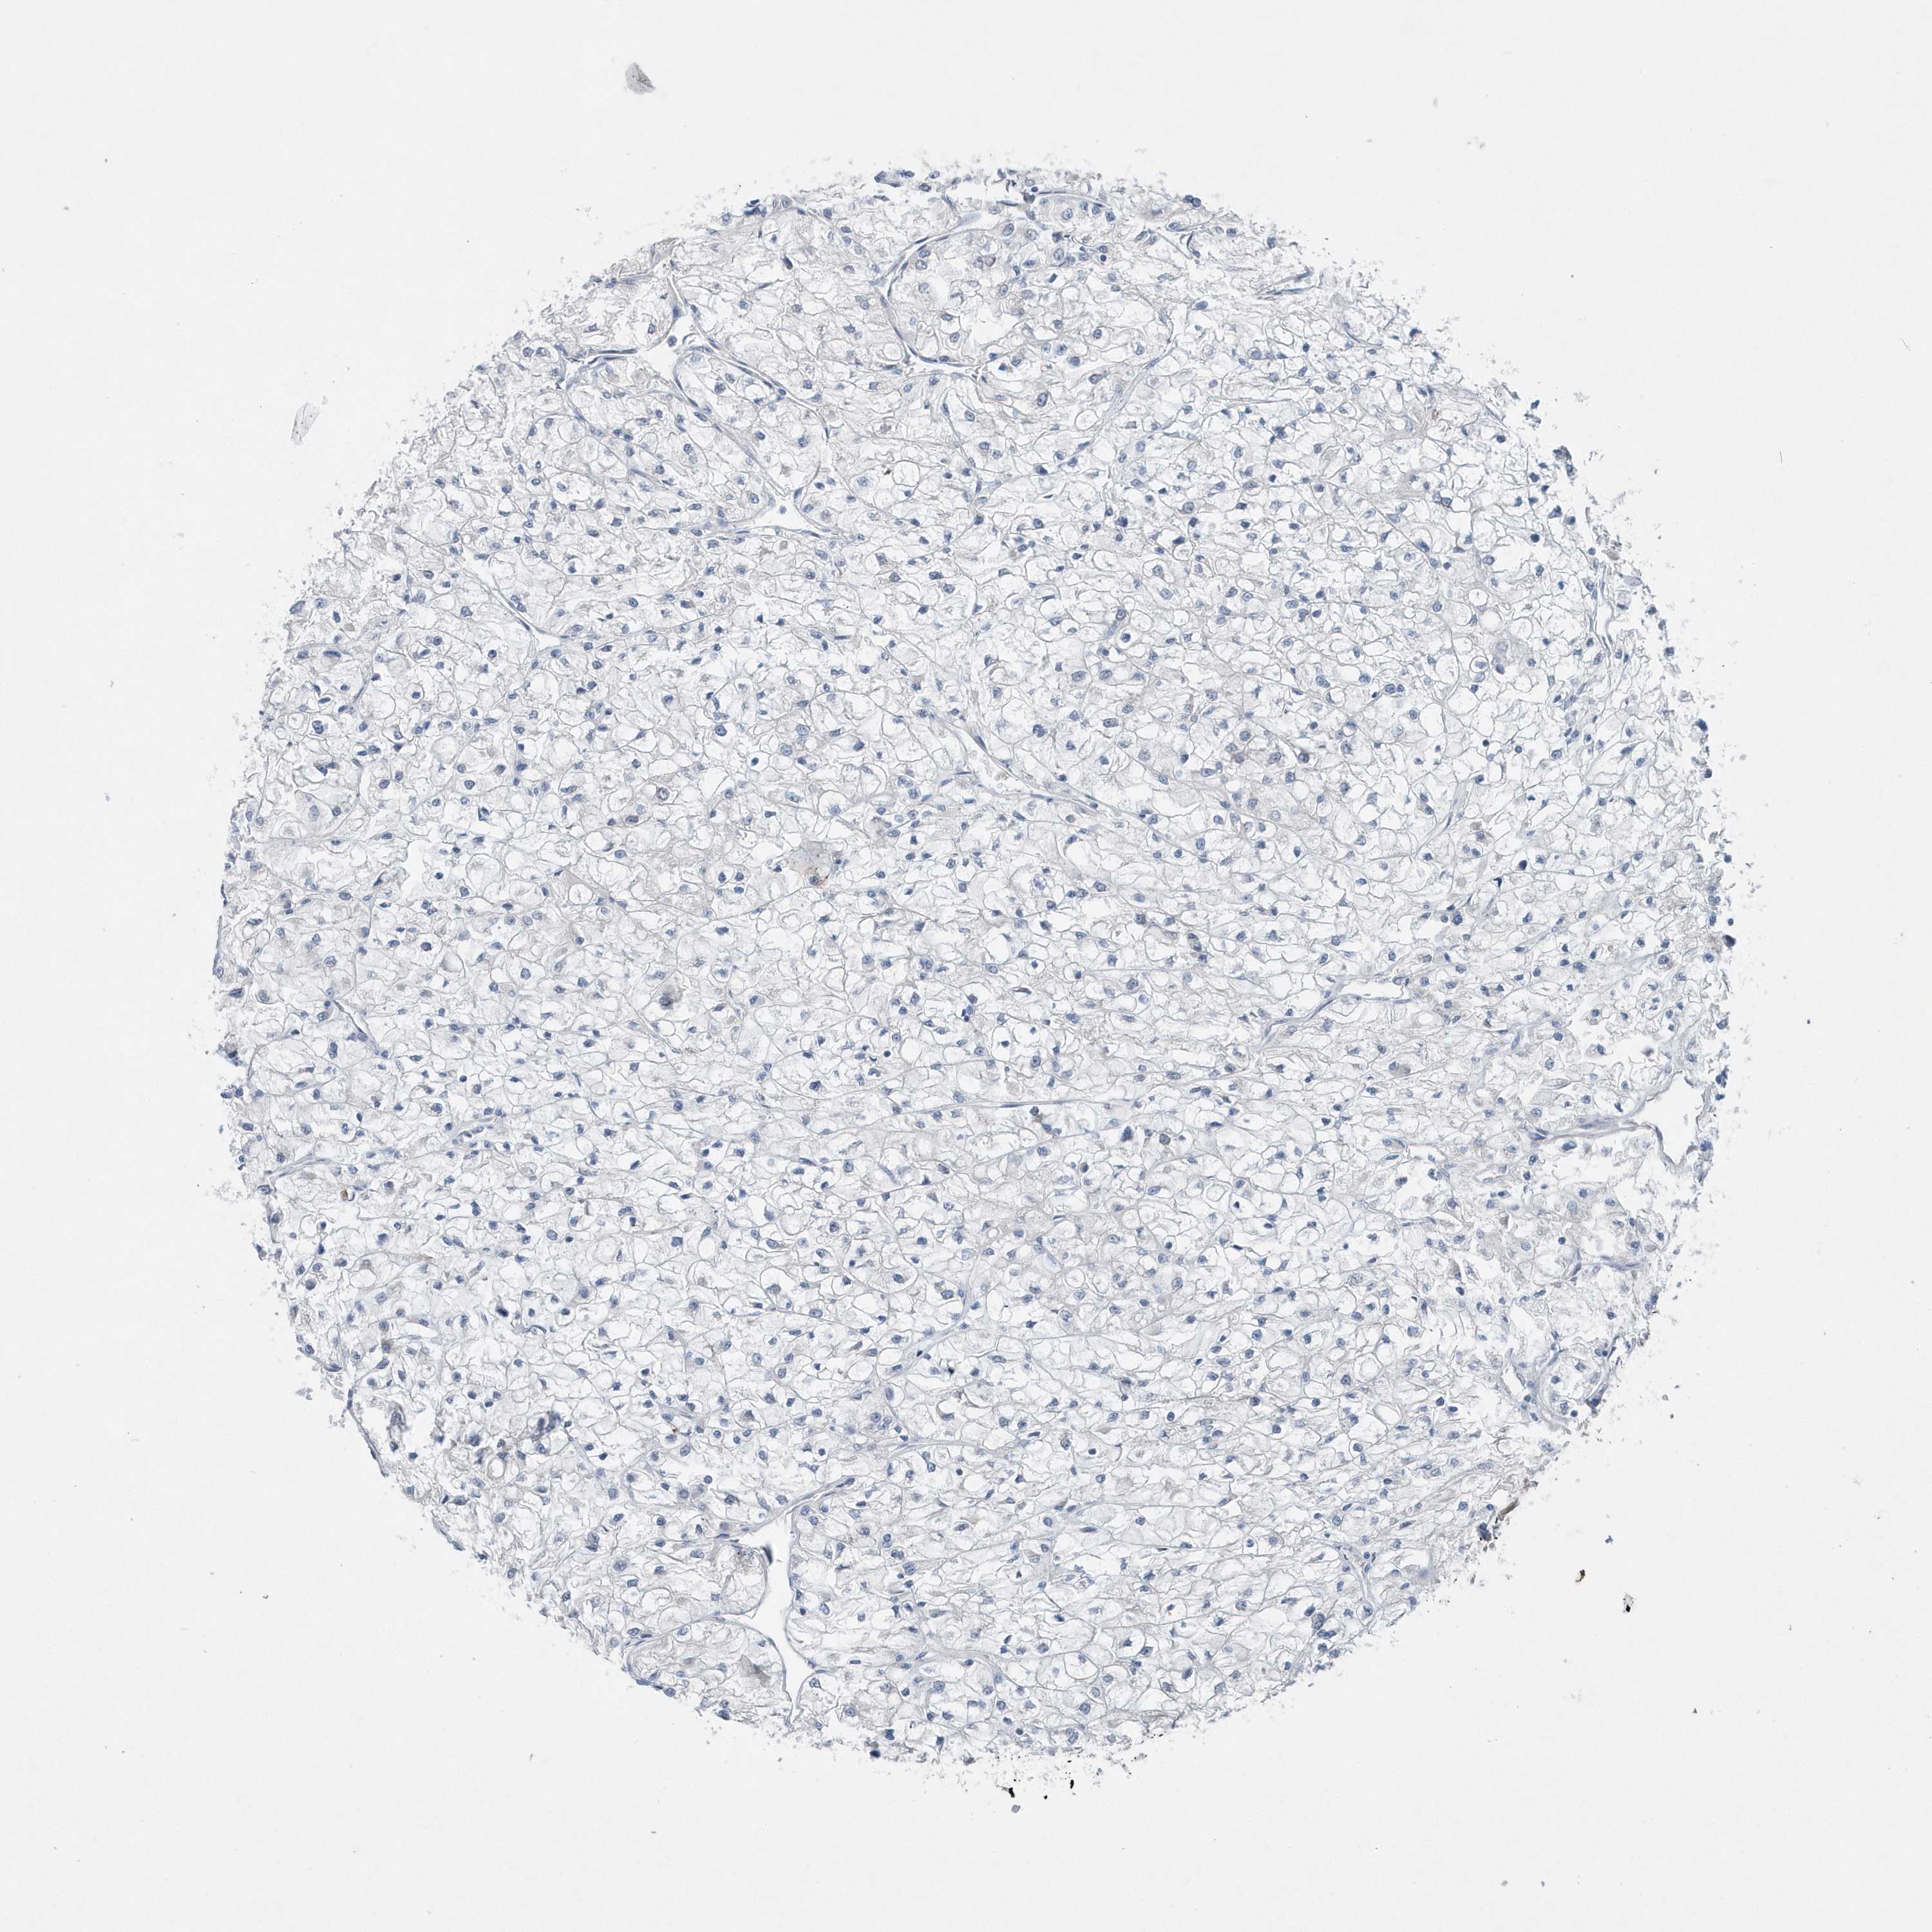

KIDNEY RENAL CLEAR CELL CARCINOMA (VALIDATION) - Interactive survival scatter ploti

The Survival Scatter plot shows the clinical status (i.e. dead or alive) for all individuals in the patient cohort, based on the same data that underlies the corresponding Kaplan-Meier plots. Patients that are alive at last time for follow-up are shown in blue and patients who have died during the study are shown in red.

The x-axis shows the expression levels (FPKM) of the investigated gene in the tumor tissue at the time of diagnosis. The y-axis shows the follow-up time after diagnosis (years). Both axes are complimented with kernel density curves demonstrating the data density over the axes. The top density plot shows the expression levels (FPKM) distribution among dead (red) and alive patients (blue). The right density plot shows the data density of the survived years of dead patients with high and low expression levels respectively, stratified using the cutoff indicated by the vertical dashed line through the Survival Scatter plot. This cutoff is automatically defined based on the FPKM cutoff that minimizes the p-score. The cutoff can be changed by dragging the vertical line or by entering a cutoff value in the square labeled "Current cut-off".

Under the Survival Scatter plot the p-score landscape (black curve; left axis) is shown together with dead median separation (red curve; right axis). Dead median separation is the difference in median mRNA expression between patients who have died with high and low expression, respectively. It is calculated as follows: median FPKM expression of dead patients with high expression - median FPKM expression of dead patients with low expression. This is intended to aid the user in visually exploring custom cutoffs and the associated p-scores and dead median separation.

Individual patient data is displayed and can be filtered by clicking on one or more of the category buttons on the top of the page. Categories describing expression level and patient information include: high, low, alive, dead, female, male and tumor stages. The scale of the x-axis can be toggled between linear and log-scale by clicking on the "x log" button. Mouse-over function shows TCGA ID, patient information and mRNA expression (FPKM) for each patient.

& Survival analysisi

Kaplan-Meier plots summarize results from analysis of correlation between mRNA expression level and patient survival. Patients were divided based on level of expression into one of the two groups "low" (under cut off) or "high" (over cut off). X-axis shows time for survival (years) and y-axis shows the probability of survival, where 1.0 corresponds to 100 percent.

MCC is validated prognostic, high expression is favorable in Kidney Renal Clear Cell Carcinoma (validation)

Best expression cut offi

: 6.25

P scorei

N/A

5-year survival highi

For melanoma and glioma, 3-year survival is shown.

5-year survival lowi

TCGA RNA samplesi

RNA-seq data is reported as average FPKM (number Fragments Per Kilobase of exon per Million reads), generated by the The Cancer Genome Atlas (TCGA) .

Normal distribution across the dataset is visualized with box plots, shown as median and 25th and 75th percentiles. Points are displayed as outliers if they are above or below 1.5 times the interquartile range. FPKM values of the individual samples are presented next to the box plot.

Average pTPM 7.6

Number of samples 100